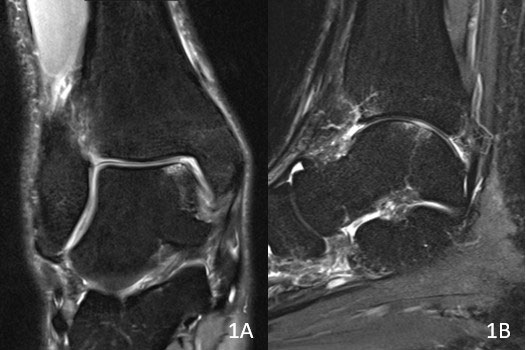

Die ärztliche Befragung gibt anhand der Symptome erste Hinweise auf einen Knorpelschaden. Eine Röntgenuntersuchung ermöglicht die genaue Analyse der Knochen und der Gelenkstellungen unter Belastung. Mögliche Anzeichen für eine Arthrose lassen sich hiermit auch bereits feststellen. Zur weiteren Beurteilung des Knorpelschadens inklusive der Bänder und Sehnen dient eine Magnetresonanztomographie (MRT bzw. engl. MRI für magnetic resonance imaging).

Bild: Universitätsklinik Balgrist

Zur weiteren Beurteilung des Knorpelschadens inklusive der Bänder und Sehnen dient eine Magnetresonanztomographie (MRT bzw. engl. MRI für magnetic resonance imaging).